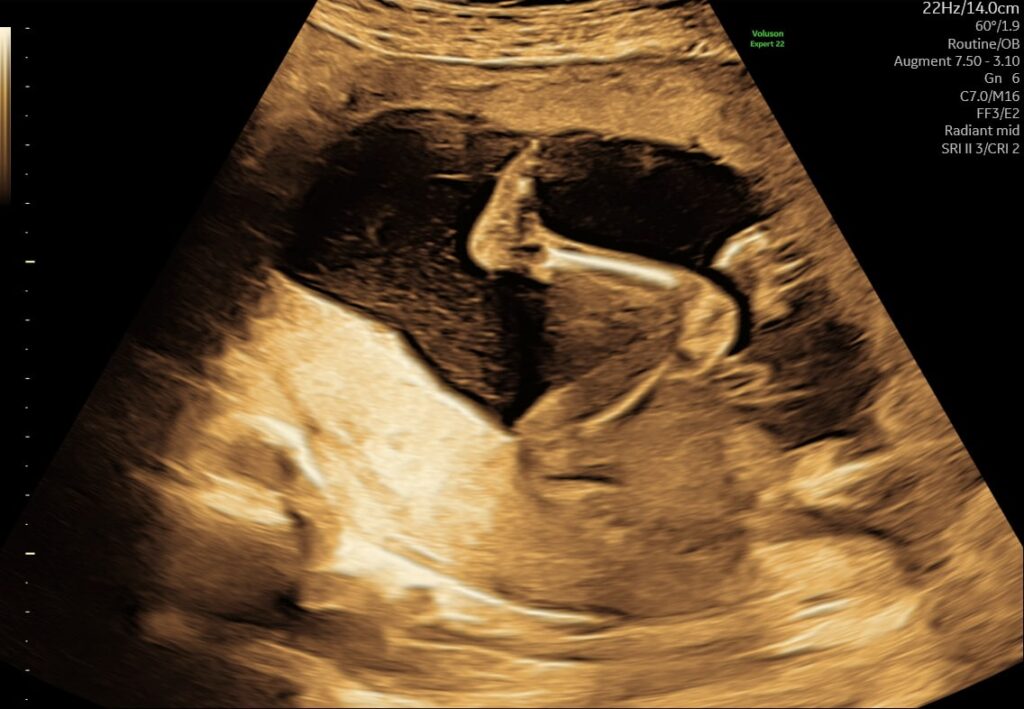

I uge 24 vejer fosteret omkring 600–650 gram og måler cirka 30–31 cm fra hoved til hæl. Det lille menneske udvikler sig hurtigt, og mange af de vitale organer bliver nu mere funktionsdygtige.